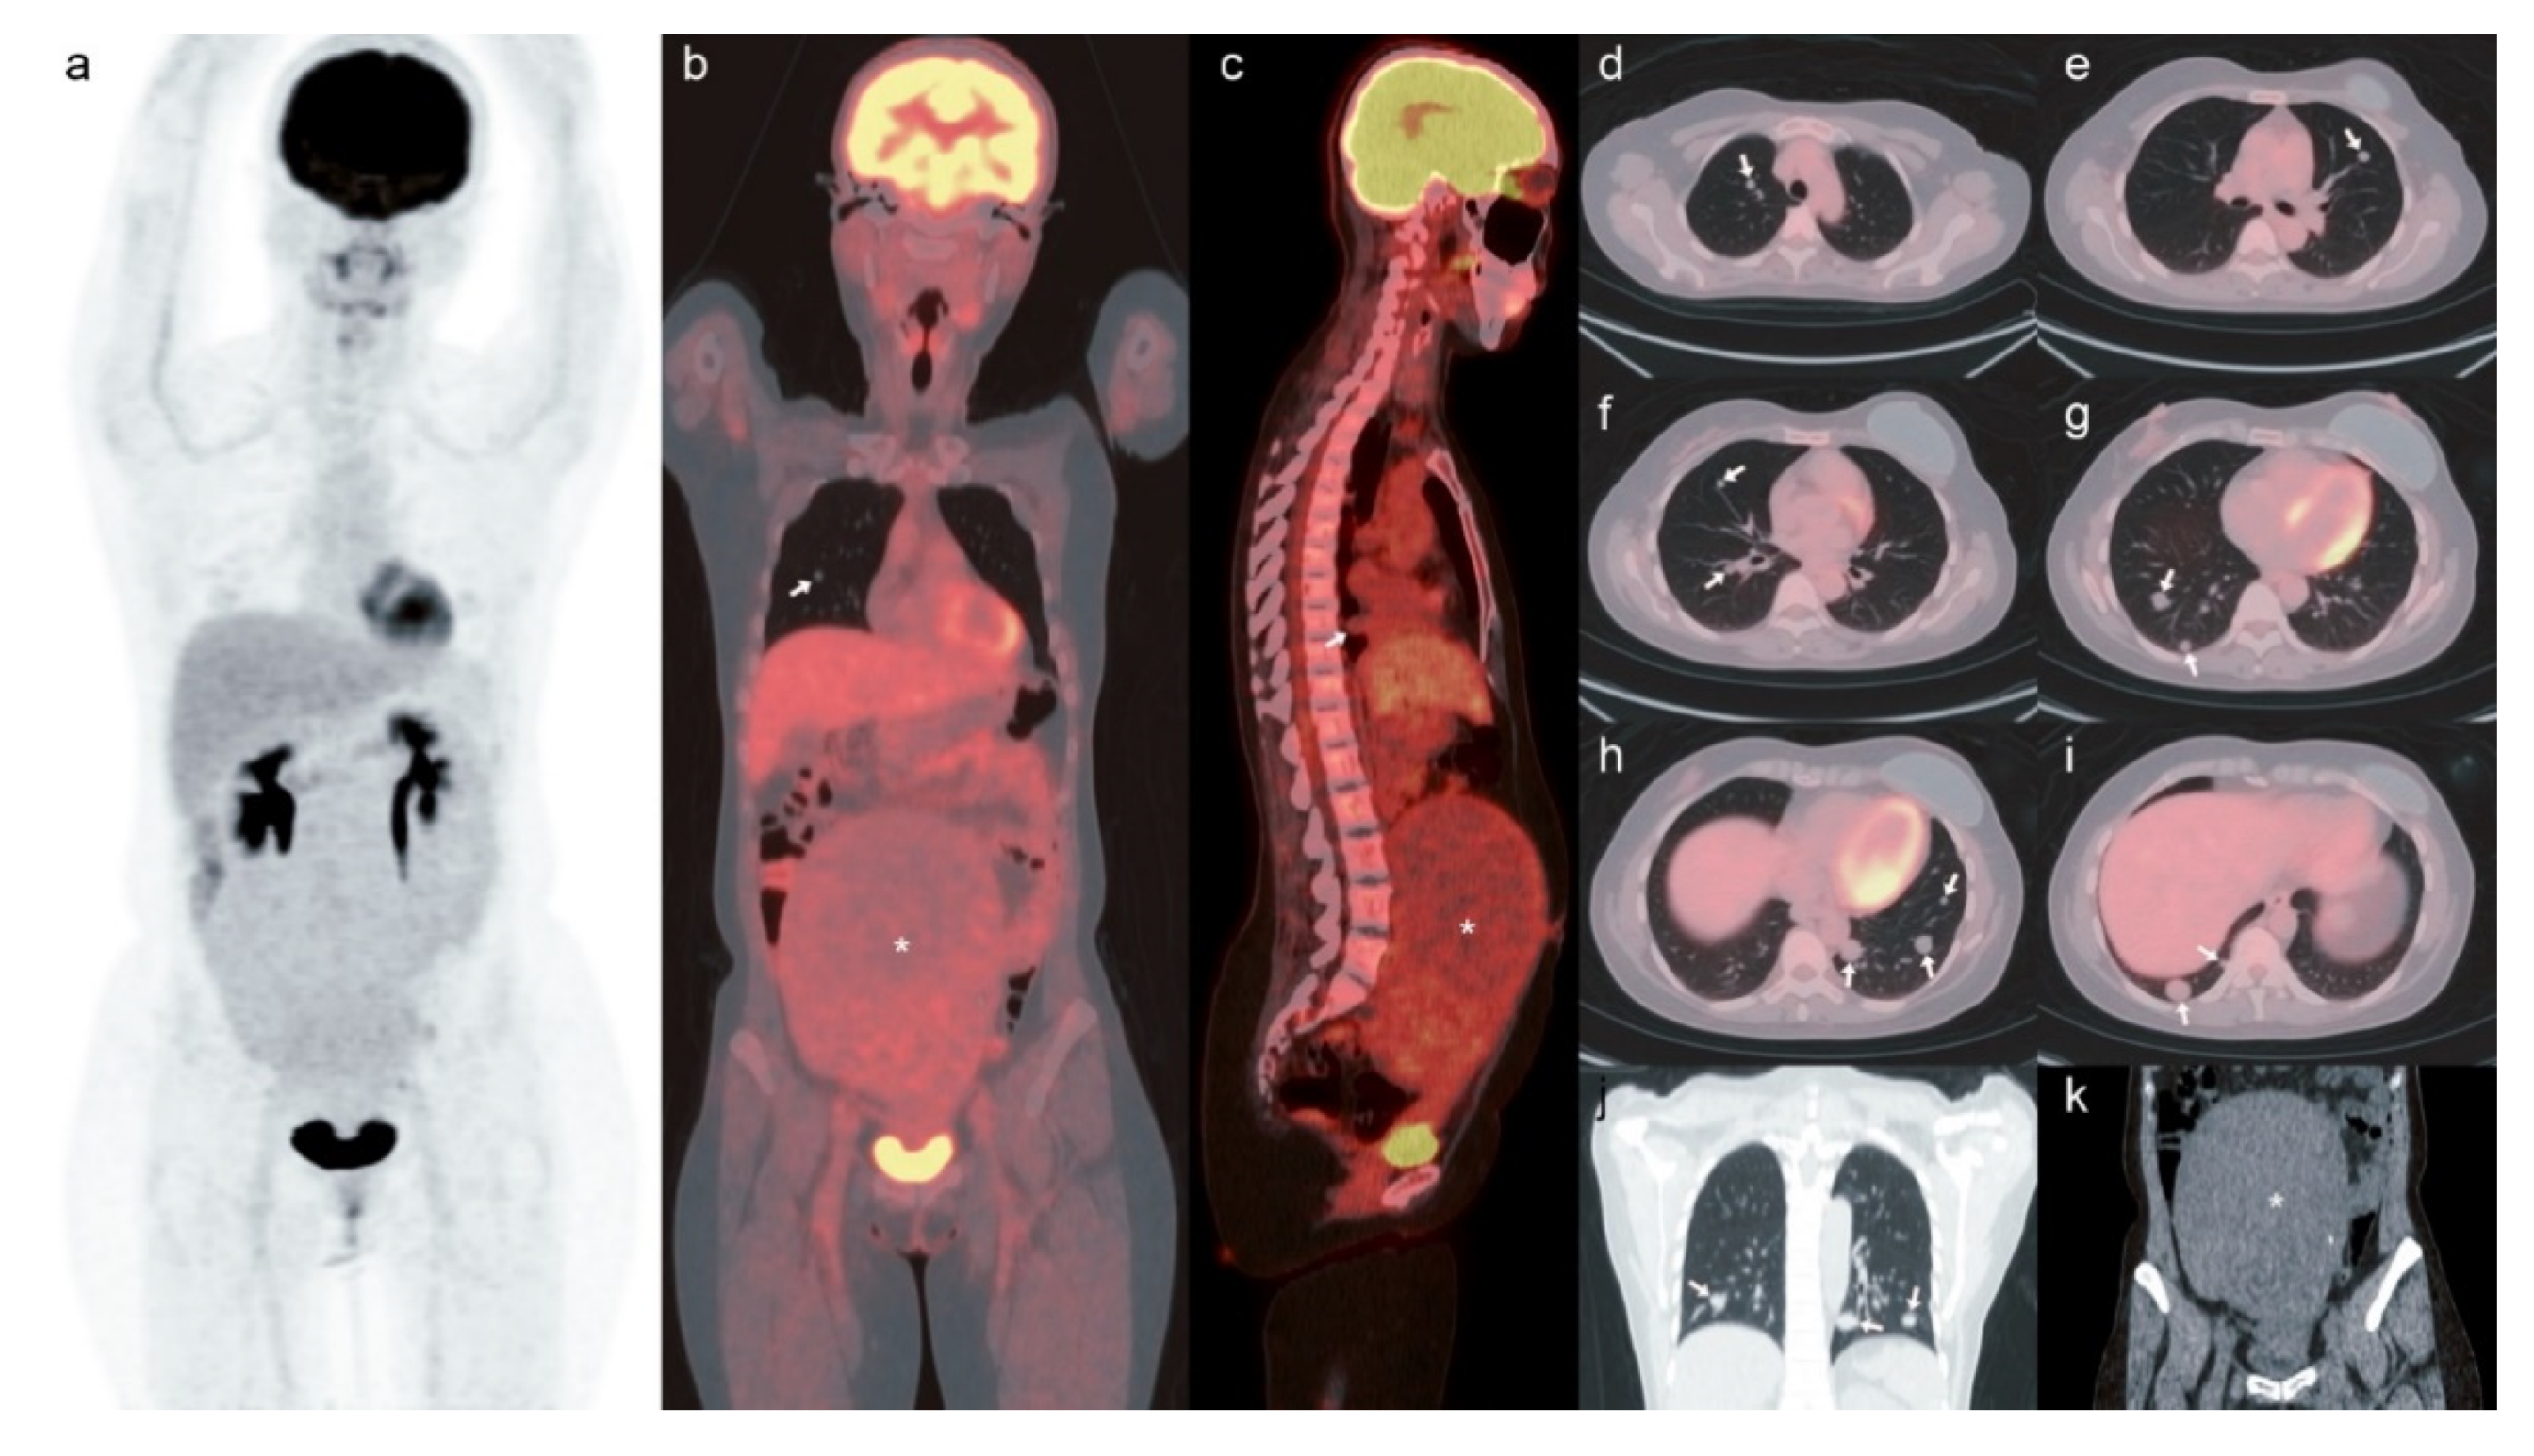

[18F]-FDG PET/CT of the Pulmonary Benign Metastasizing Leiomyoma in a Breast Cancer Patient: A Case Report

Kao, C.-H.; Gao, H.-W.; Ko, K.-H.; Liao, G.-S.; Tsai, C.-J. [18F]-FDG PET/CT of the Pulmonary Benign Metastasizing Leiomyoma in a Breast Cancer Patient: A Case Report. Surgeries 2021, 2, 231-236. https://doi.org/10.3390/surgeries2030023